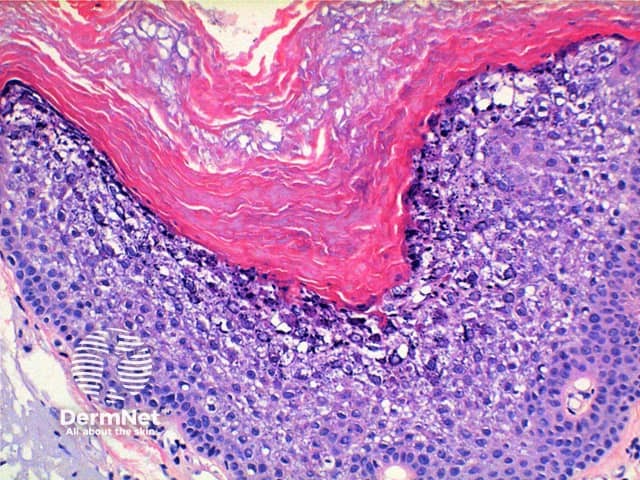

Low power view of histology of epidermolytic hyperkeratosis demonstrates hyperkeratosis and epidermal hyperplasia of varying degrees (Figure 1). The diagnostic features include a characteristic vacuolar degeneration with hypergranulosis of the stratum granulosum and stratum spinosum (Figures 2 and 3).